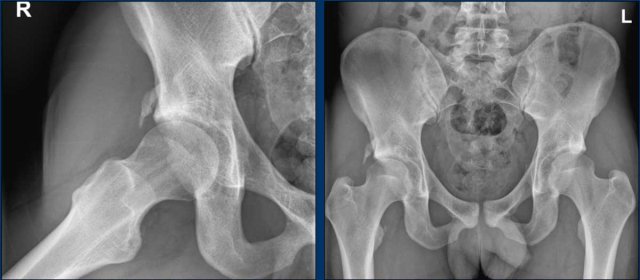

A 20-year-old gymnast with hip complaints.

On the AP view the femoral head-neck region looks normal.

On the Dunn view there is Cam morphology on both sides (arrows).